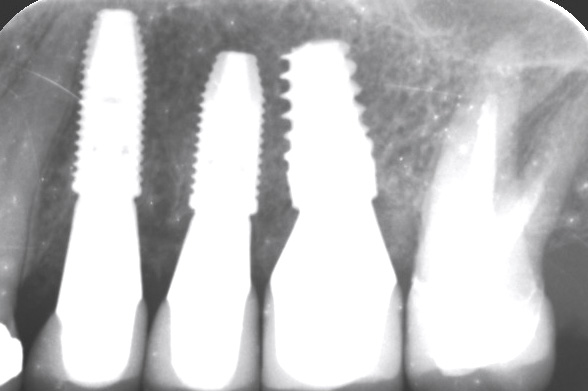

13/13 - Control x-ray image of the placed implants after 7 months